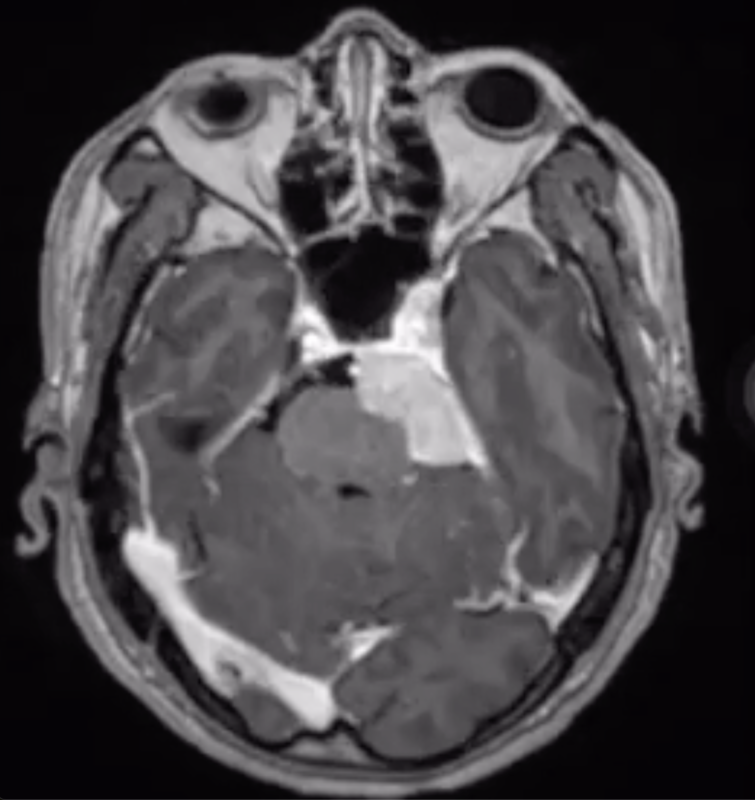

錐体斜台部髄膜腫

引き続きハノイでの症例です。福島先生がよくおっしゃっていた「脳外科の手術で一番難しい」錐体斜台部髄膜腫。アプローチそのものに非常に難渋しましたが、ほぼ全摘出できました。